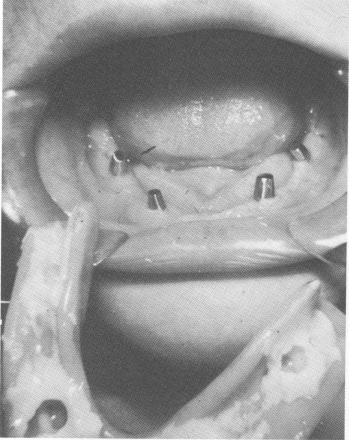

The tissues were adapted and sutured with simple surgical ties (Fig. 11-141) . When the sutures were removed (Fig. 11-142), the patient's old denture was hollowed out, lined with a soft tissue reliner, and used as a temporary splint until the final prosthesis could be fabricated (Fig. 11-143).

Fig. 11-143. The patient's old denture, relined with soft tissue conditioner, was placed temporarily over the implants. To make the posts parallel prior to final impressions, they were ground directly in the mouth.

1 Mandibular old denture relined with soft tissue conditioner